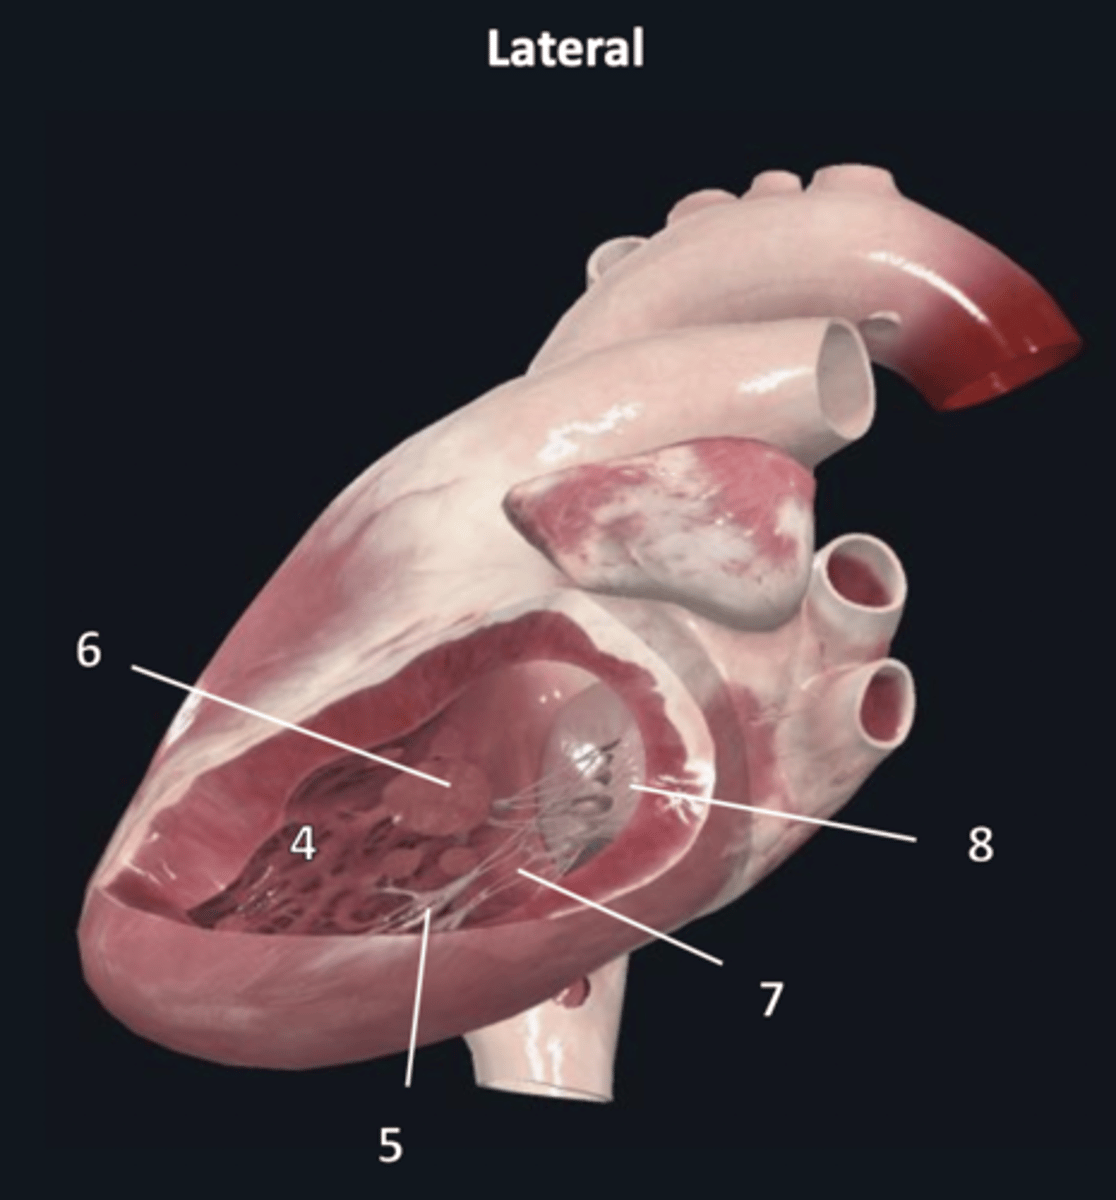

left atrium

1

left auricle

2

left ventricle

3

trabeculae carneae

4

inferior papillary muscle

5

superior papillary muscle

6

chordae tendineae

7

left atrioventricular valve

8 (opening)

aortic semilunar valve

9 (opening)